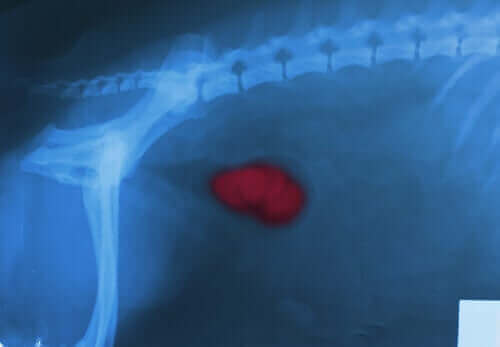

Neoplazma

Habis veya iyi huylu olan neoplazmalar, vücudun belirli bölgelerinde anormal ve aşırı doku büyümesidir. Örneğin, prostat hiperplazisi, hemanjiyom veya hemanjiyosarkom sıklıkla kanamaya neden olur.